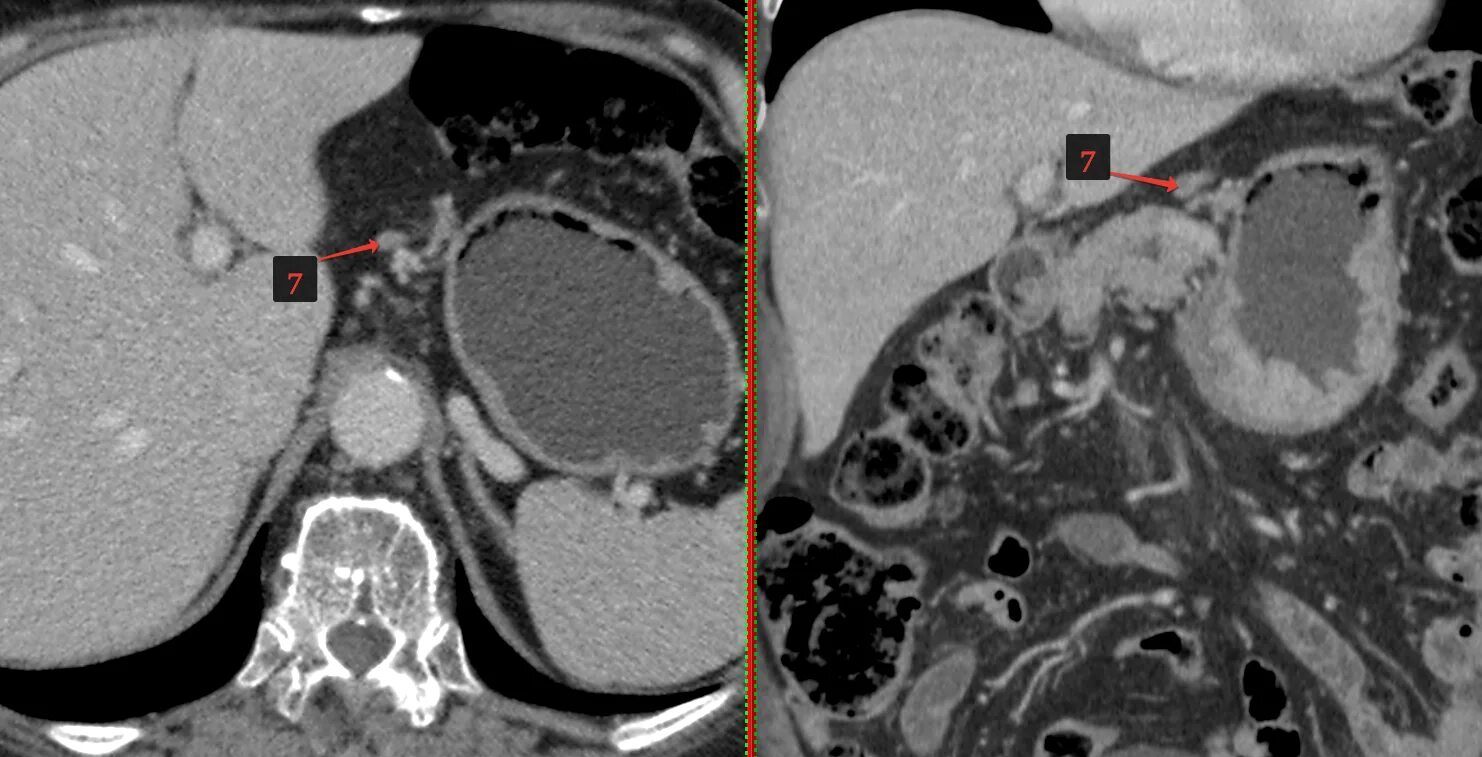

Язва желудка кт